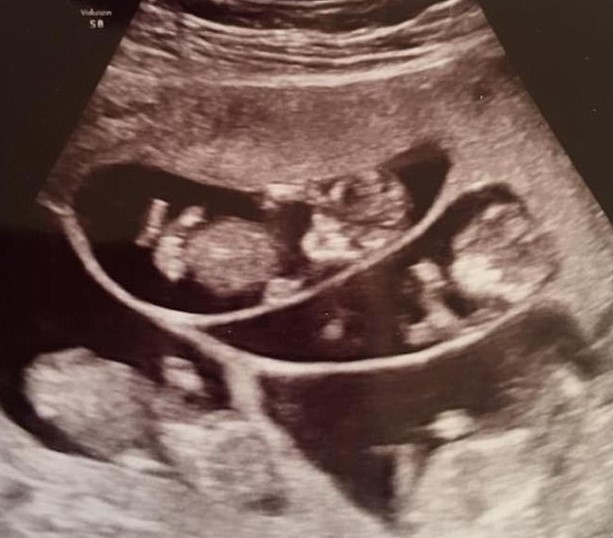

在一次簡單的檢查中,這對夫婦迎來了巨大的驚喜

從波比到醫生,這必須是一次簡單的檢查。然而,她剛做的超聲波檢查沒有顯示一個,也沒有顯示兩個,更沒有顯示三個……而是顯示了七個胚胎!這對波比來說無疑是一個巨大的挑戰,養育一個孩子本來就不容易,更何況是七個嬰兒……想像一下,要讓七個嬰兒在一個母親的子宮裡成長!當時,未來的母親肯定感到分身乏術,但這只是第一步。